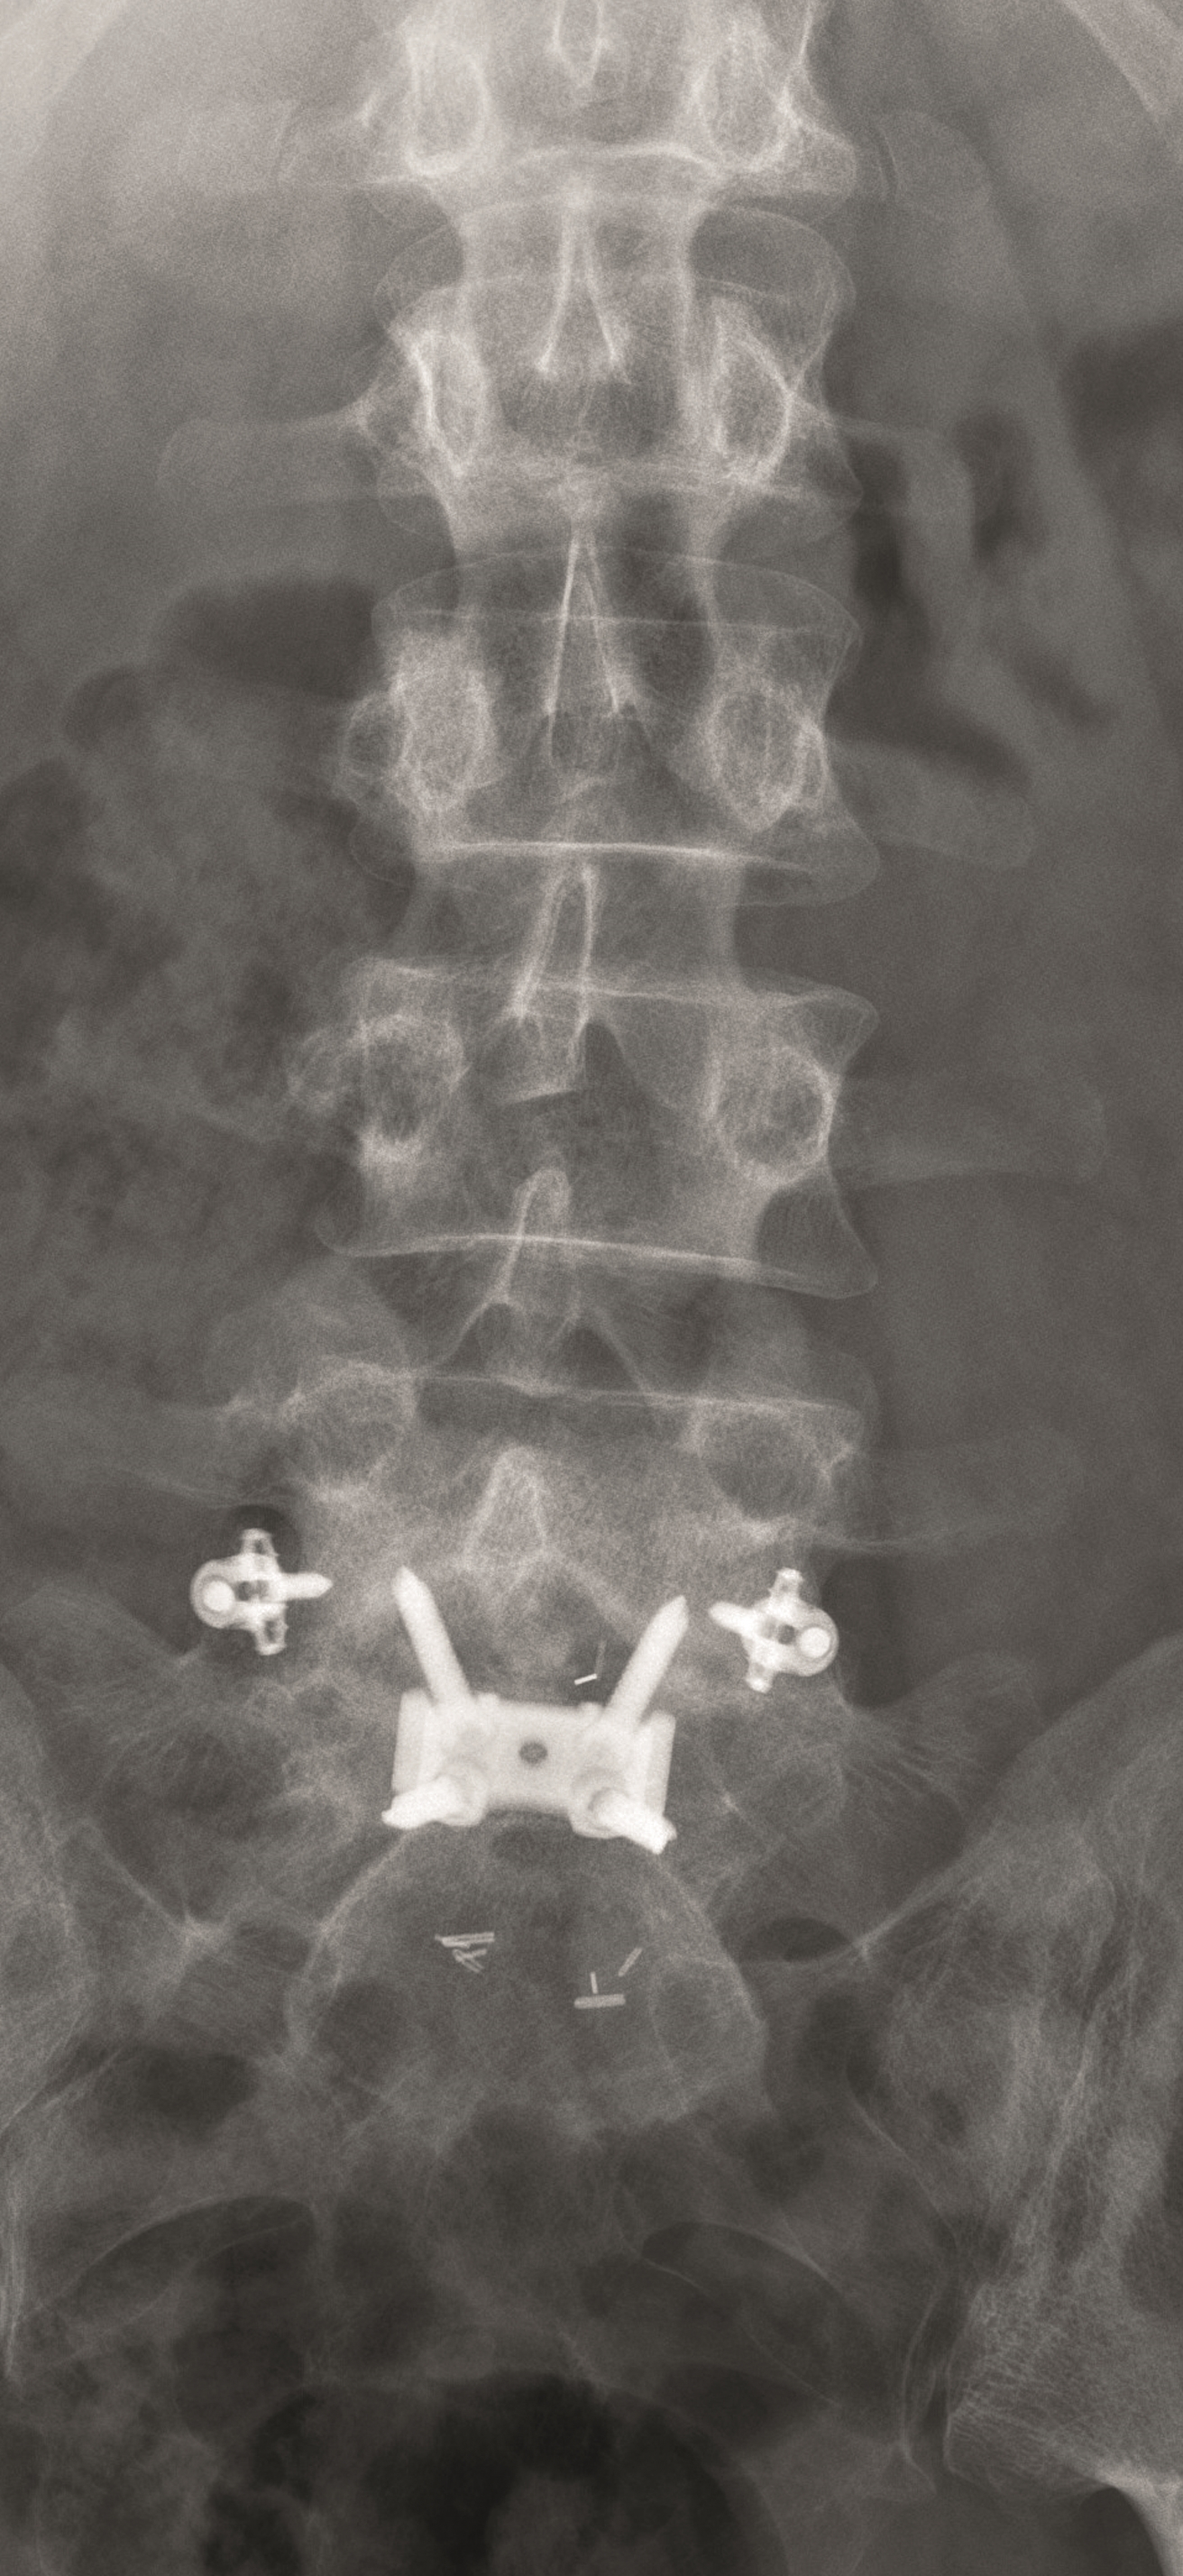

A less invasive approach was used with Insight Retractor using the bilateral Facet Wedge. No bone graft. X-ray follow-up after 3 months and CT assessment after 6 months (Fig 18-19).